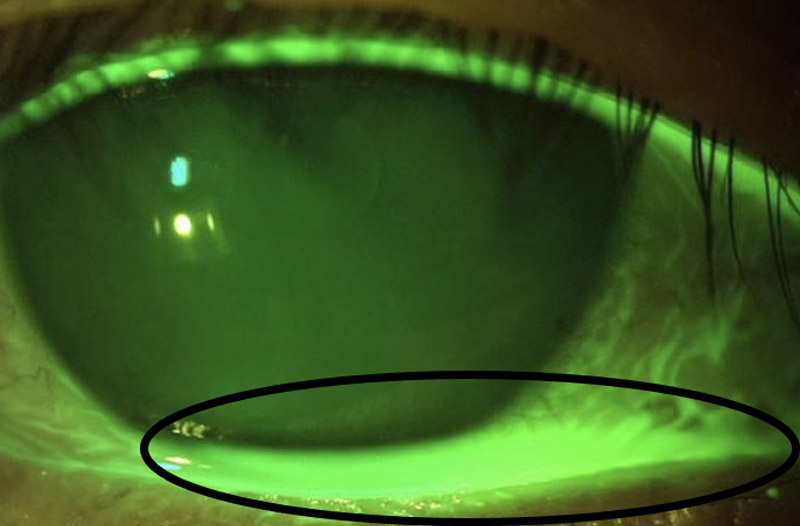

黒目の下~下まぶたの間にたくさん涙が溜まっています。

黒目の下から下まぶたの間にたくさん涙が溜まっています。